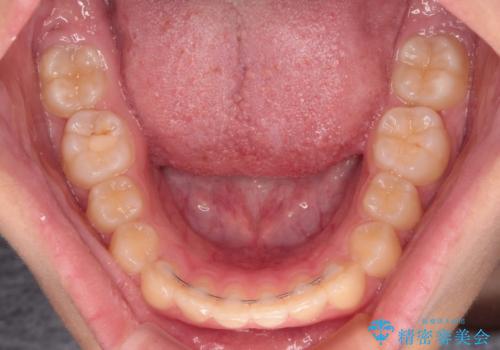

- ヨーロッパにてインビザライン矯正を始めたものの、日本に転居することになり、治療の継続を希望して来院された患者様です。

治療計画に無理がなく、現地担当医と速やかに連絡が取れるとのことで、インビザライン社での転医手続きを行い、継続して治療を行うこととしました。

舌の突出癖により、上下前歯が非接触となっていたため、トレーニングを徹底的に指導し、安定した咬み合わせにより終了させることができました。